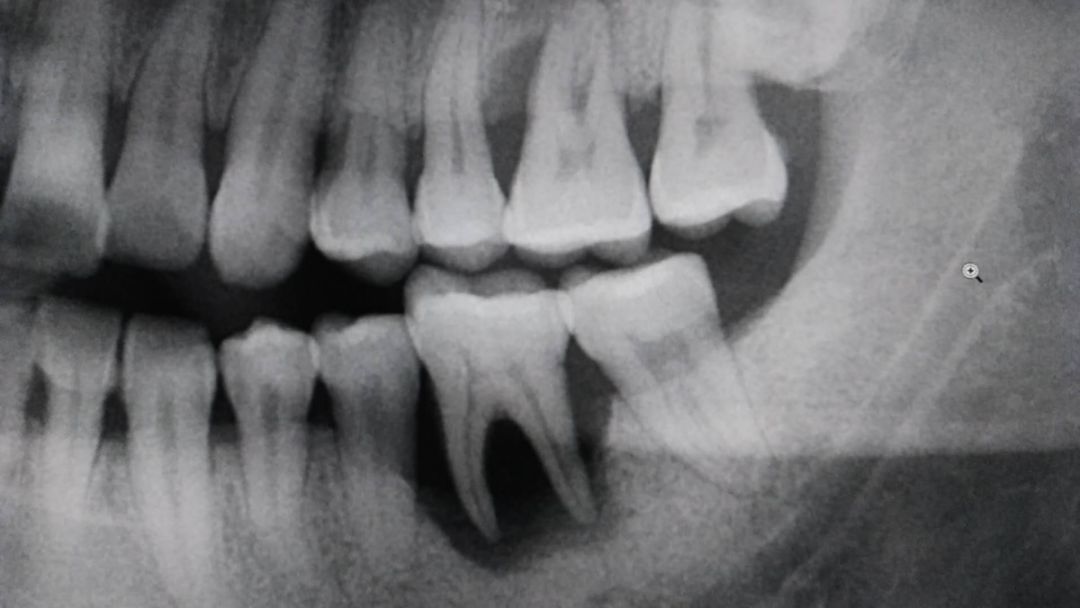

(如图,患者左下第一磨牙(即下颌倒数第二颗)的牙槽骨已经完全吸收,还是个比较标准的“凹”字型坑,这形状在牙签使用频率高的牙齿上多见。)

口腔医生介绍道,牙齿可以看成一颗颗的树,而它们生长的土壤就是上下颌骨的牙槽骨部分,树会因水土流失难以存活,牙齿也会因牙槽骨吸收而难以保留。